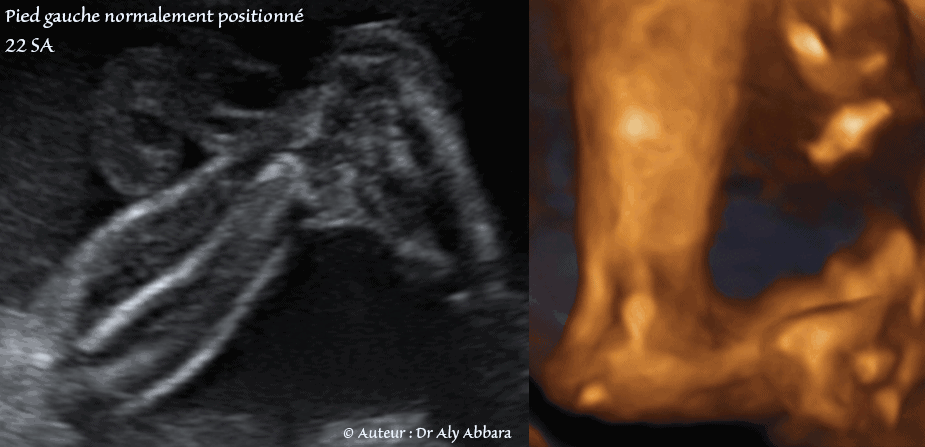

Pied gauche en position normale - 22 SA

Images échographiques en 2D et en 3D comparant l'aspect du pied droit bot varus au pied collatéral en position normale.

Dans le pied varus la plante du pied est retourné sur son axe longitudinal pour regarder vers le plan sagittal médian du corps foetal (regarder en dedans) ; il s'agit de la position normale du pied dans le stade embryonnaire (Embryon de 8SA + 2J, Embryon de 8SA + 6J) ; donc chez le foetus à pied bot varus, cette position embryonnaire est conservée durant toute la vie in-utero.

Échographiquement, si le pied est varus, la coupe passant sagittalement par l'axe longitudinale de la jambe permet de faire apparaître la plante du pied du même membre inférieur, au lieu voir le profil de ce pied.